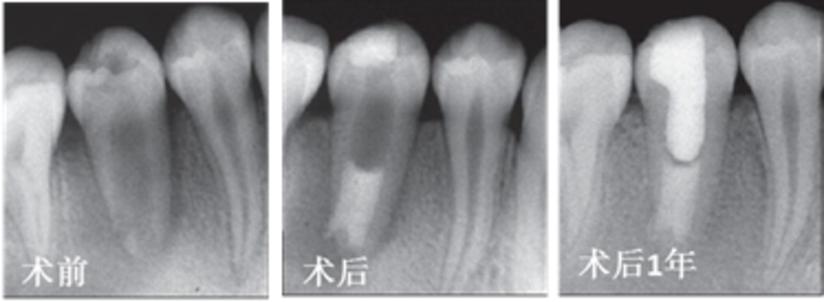

为了让治疗后的牙齿可以继续发育,人们发明了一种名叫“牙髓血运重建术”的治疗方法,这个治疗方法是通过对感染坏死的年轻恒牙联合用药进行彻底的消毒,然后刺激牙齿根尖周组织出血,待根尖下方周围组织形成血凝块后用材料严密封闭牙齿上方,促进年轻恒牙的牙根管腔内新生组织再生。新生组织有助于牙根长度的增加、管壁的增厚和根尖孔的闭合,从而达到接近正常牙根发育的效果。